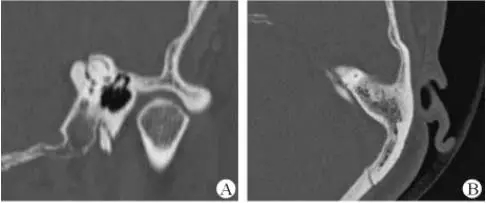

1、上半規(guī)管裂綜合征

內(nèi)耳結(jié)構(gòu)非常微妙。即使是內(nèi)耳中大頭針樣的孔洞也能造成平衡失調(diào)。患者常常不敢進(jìn)行如走路或轉(zhuǎn)頭的日常活動。此罕見疾病,醫(yī)學(xué)專家預(yù)估至少影響著人口的1%。可造成惡心,眩暈以及對噪聲極高的敏感性。病人還常常抱怨他們能聽到血管跳動的聲音。其中一位患者曾告訴耳科專家,他都能聽到自己轉(zhuǎn)動眼睛的聲音。

診斷及治療

醫(yī)生若懷疑此病將會安排內(nèi)耳CT掃描。在大多數(shù)案例中,一旦此病被耳鼻喉科醫(yī)生或其它聽力健康專家確診,則可實(shí)行手術(shù)治療。外科手術(shù)風(fēng)險(xiǎn)包含聽力損失以及神經(jīng)損傷;重建及復(fù)原需內(nèi)耳的治療以及大腦的重塑。

2、膽脂瘤

另一個不常見的疾病叫膽脂瘤,發(fā)病率為1/10000,這個“腫瘤”在內(nèi)耳中逐漸生長。盡管不是惡性的,但也能導(dǎo)致永久性的聽力損失以及其它嚴(yán)重的疾病,比如腦膜炎。癥狀是有臭味的耵聹以及聽力損失。